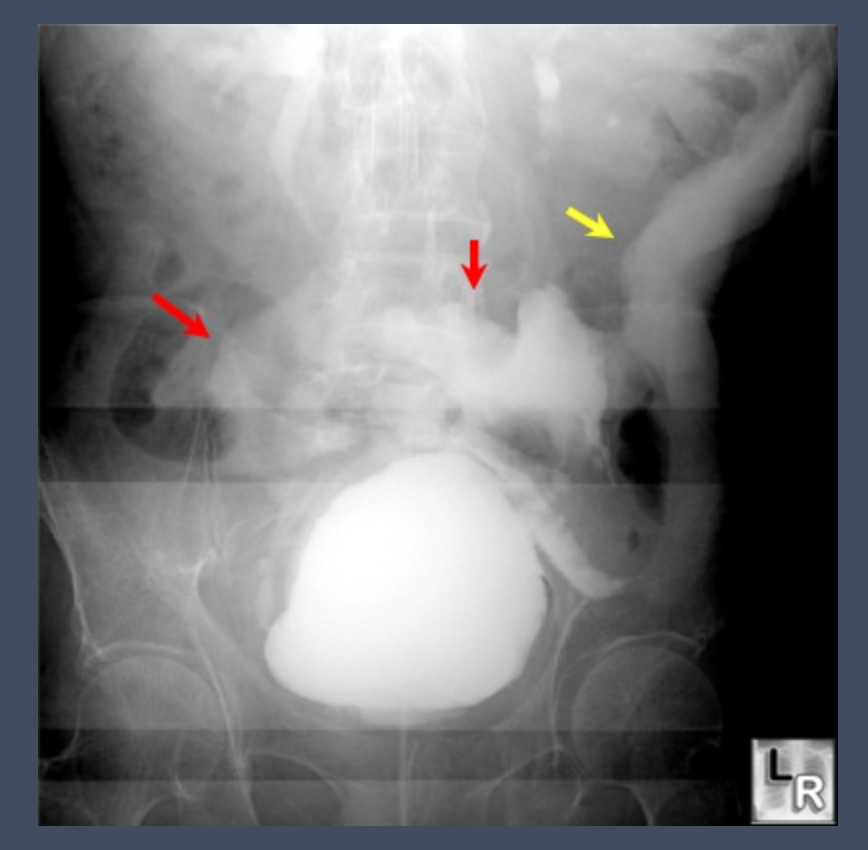

Cerebral palsy patient with blunt abdominal trauma and haematuria.

Postvoid film shows a flame-shaped density adjacent to lateral walls of bladder representing extra-peritoneal contrast from a bladder rupture.

Case courtesy of Dr Ali Nourian, Radiopaedia.org, rID: 27806

Name the radiologic findings of extraperitoneal bladder rupture in VCUG?

1- Pear-shaped bladder

2- Flame-shaped contrast extravasation into perivesical fat best seen on postvoid films

3- Paralytic ileus